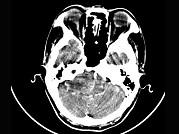

问题 女,45岁,右耳听力下降半年余,CT检查如图,最可能诊断为()

选项 A.继发性胆脂瘤 B.脑膜瘤 C.三叉神经瘤 D.原发性胆脂瘤 E.听神经瘤

答案 E